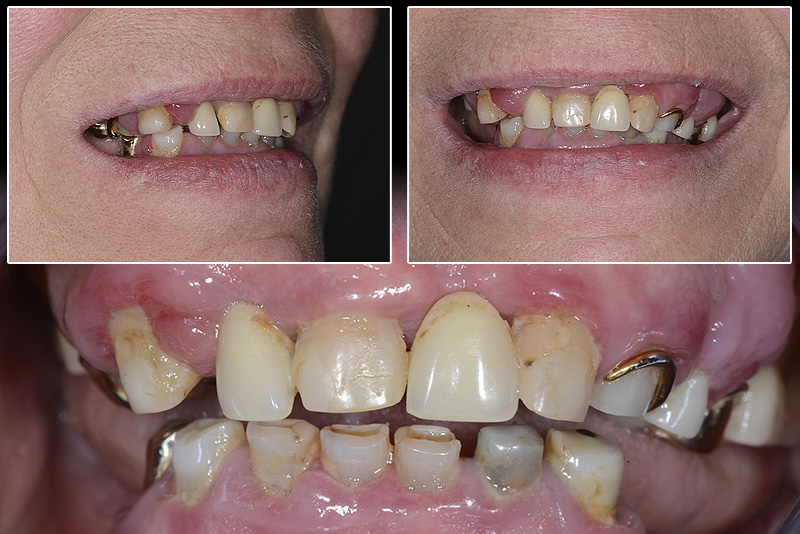

PREMESSA: in seguito all’estrazione dell’incisivo laterale superiore di destra, resasi necessaria per cause batteriche, si decide di affrontare il caso con il posizionamento di un impianto in sostituzione dell’elemento mancante dopo guarigione del sito infetto. Con tecniche rigenerative sia dei tessuti ossei mancanti a causa dell’infezione pregressa, sia dei tessuti gengivali che appaiono inizialmente troppo spostati in alto, si ripristina una corretta morfologia delle parabole (contorni) gengivali e delle papille interdentali (triangoli di gengiva tra due denti vicini).

Vengono utilizzati 2 tipi di provvisori: il primo, cementato ai denti vicini, viene utilizzato dal momento dell’estrazione del dente fino ad impianto osteointegrato (circa 6 mesi); il secondo, avvitato direttamente all’impianto, ha una funzione di prova estetica ma soprattutto di guida per la maturazione dei tessuti gengivali peri-implantari portandoli verso la maturazione completa prima di posizionare la corona finale in disilicato di litio.